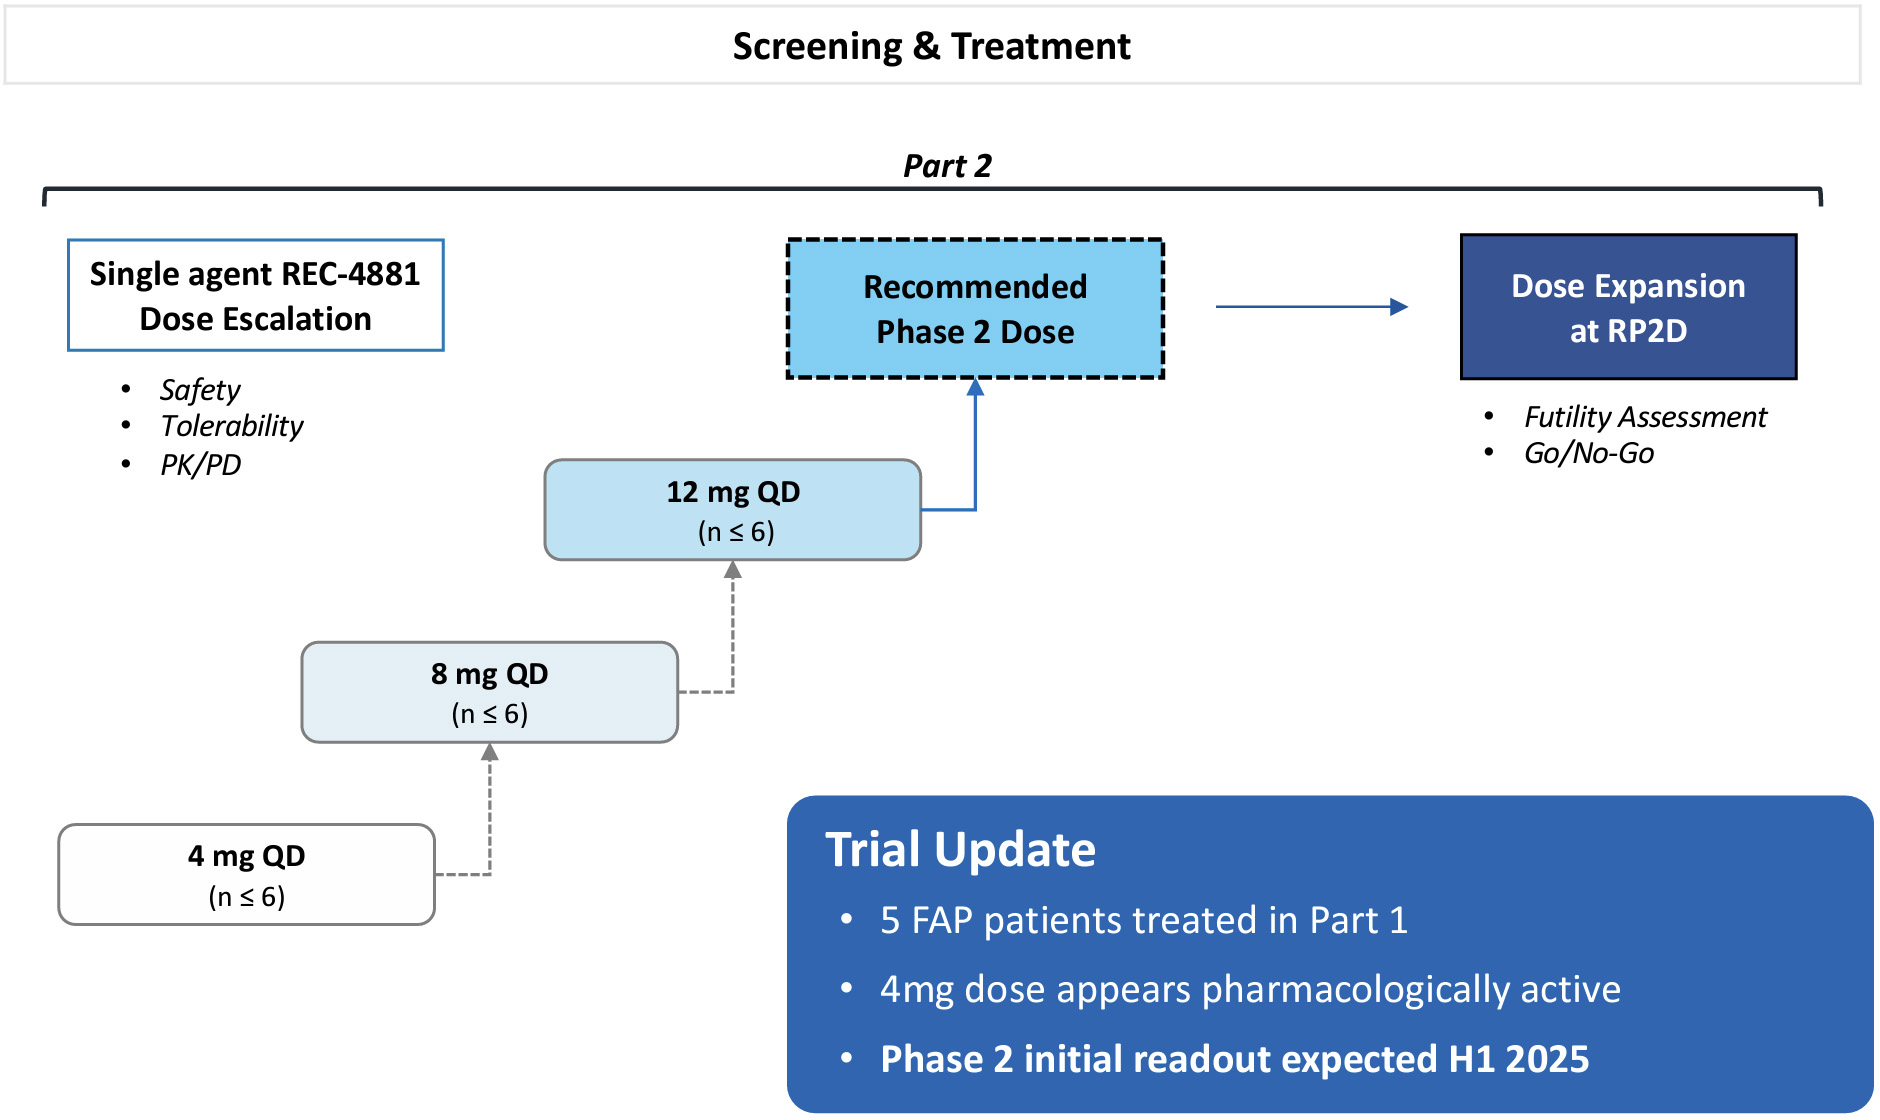

| | What’s more, the signs of AI-enabled point-solutions are already plentiful across our industry: •Protein folding •Scaled protein-ligand interaction prediction •Generative AI for chemistry for tractable targets •The FDA is already discussing the use of LLMs for program review •Major pharma companies are drafting regulatory filings like INDs by LLMs These facts lay out a clear future where efficiencies and improvements across the many current AI-enabled point-solutions will begin to combine into integrated ‘tech-stacks’ and workflows that will result in compounding improvements in our ability to drug historically undruggable targets, understand the underlying networks of biology with increasing fidelity, fast-follow newly validated biology, characterize disease in increasingly robust ways and ultimately deliver more, better medicines to patients to alleviate suffering at scale. The question is no longer whether this sort of future is before us, but when and who will lead it. Looking Back at 2023 and Before Reflecting back on late 2013 when Recursion was founded and how far we have come, it is simultaneously incredible and unsurprising to see where we are today. Recursion was then a Utah-based startup founded by two graduate students and a professor. Our first office was a conference room in the nearby University Research Park and our first laboratory was a converted storage room. Today, Recursion is a multinational, clinical-stage company leading the transition of BioTech into TechBio. We have over 500 employees, five clinical stage programs, one of the world’s largest biological and chemical datasets and two of the largest discovery collaborations in the industry with Roche/Genentech and Bayer. And in 2023, the opportunity ahead feels so much greater than it did in 2013, that in some ways it still feels like we are just getting started. In fact, from an internal perspective, 2023 felt like one of the best years in our history. In 2023 we achieved a lot of important milestones, and a lot of things we’ve been working to build, in some cases for years, really seemed to start hitting their stride, including: Pipeline •Five phase 2 clinical-stage programs with multiple upcoming data readouts expected, including REC-994 in cerebral cavernous malformation (CCM) in Q3 2024, REC-2282 in neurofibromatosis type 2 (NF2) in Q4 2024, REC-4881 in familial adenomatous polyposis (FAP) in H1 2025, and REC-4881 in AXIN1 or APC mutant solid tumors in H1 2025 •Completed a Phase 1 study for REC-3964 in healthy volunteers for the potential treatment of Clostridioides difficile (C. difficile) infection with a favorable safety and tolerability profile •Advanced our RBM39 program in homologous recombination proficient ovarian cancer and other solid tumors to IND-enabling studies •In-licensed a program (Target Epsilon) that emerged from our fibrosis collaboration with Bayer that represents a novel approach to treating fibrotic diseases with compelling early data |

•Five phase 2 clinical-stage programs with multiple upcoming data readouts expected, including REC-994 in cerebral cavernous malformation (CCM) in Q3 2024, REC-2282 in neurofibromatosis type 2 (NF2) in Q4 2024, REC-4881 in familial adenomatous polyposis (FAP) in H1 2025, and REC-4881 in AXIN1 or APC mutant solid tumors in H1 2025